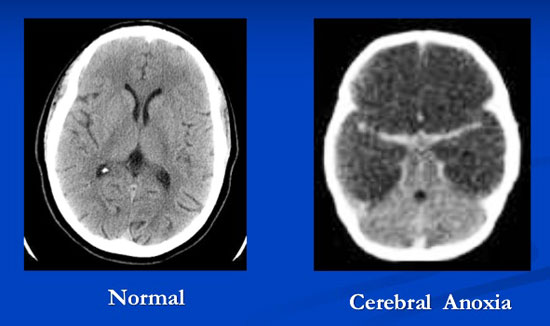

Le concept de « mort cérébrale » a été inventé en 1968. Jusque-là, on ne connaissait que deux états : vivant ou mort.

Pour pouvoir prélever des organes encore vivants, et donc capables d’être transplantés sur une nouvelle personne, les médecins créèrent en 1968 le concept de « mort cérébrale ». Une personne dont le cœur fonctionne, le sang circule, et la respiration est régulière peut donc aujourd’hui être déclarée en état de « mort cérébrale ». On sait pourtant que, dans ce cas, la plupart des fonctions vitales continuent, dont la digestion, l’excrétion (évacuation des déchets), et l’équilibre des fluides.